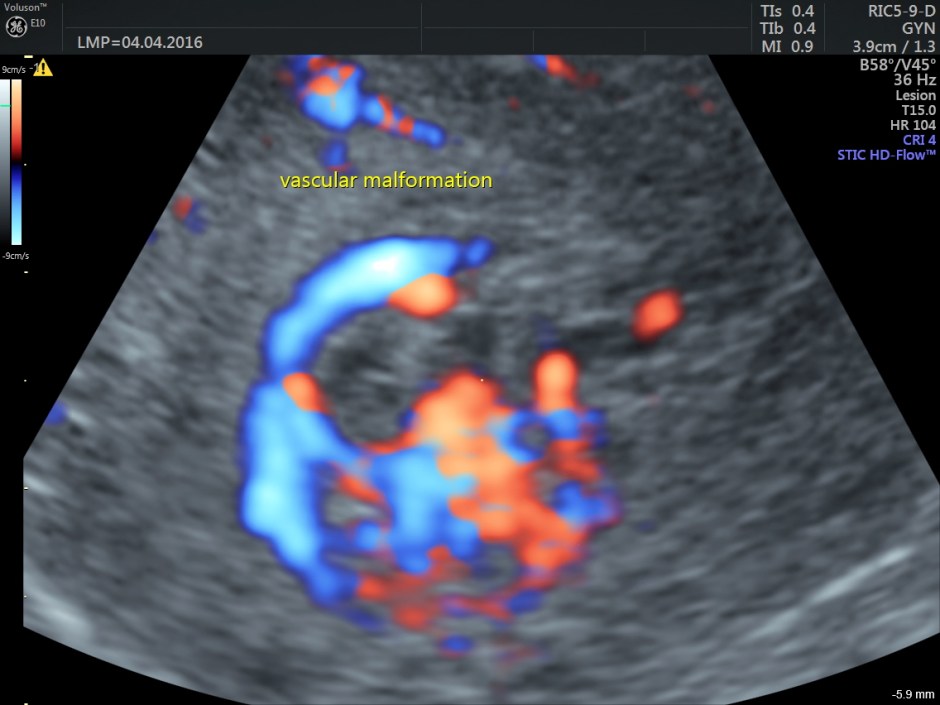

The following are the different sections of the Power Doppler reconstruction images of the trans-vaginal scan.

The following are the reconstructed 3D Power Doppler images.

The ultrasound diagnosis was a vascular malformation in the uterus .She was referred to an interventional radiologist,who did a CECT the next day.

Typically shows serpiginous/tubular anechoic structures within the myometrium with a low resistance (RI ~0.2-0.5), high velocity flow pattern on colour Doppler interrogation.